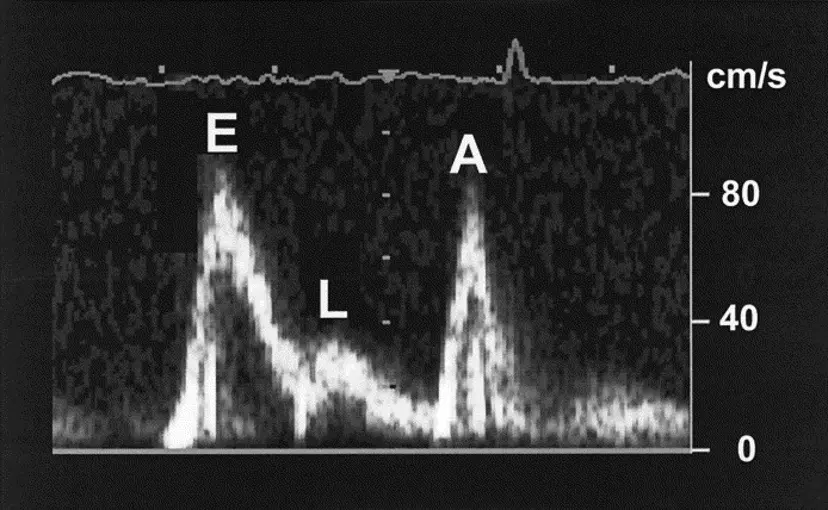

L-wave

L wave on M-mode is suggestive of marked sinus bradycardia or CHB